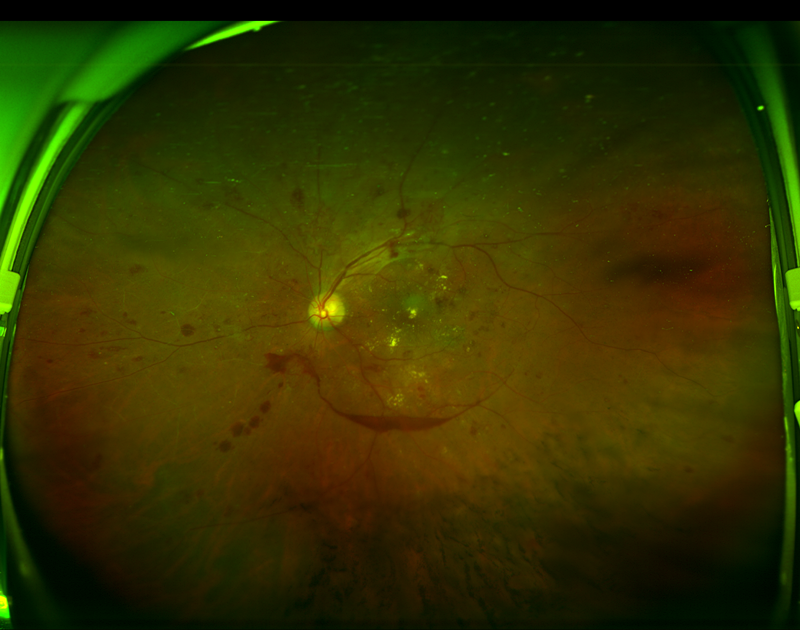

| 图一:糖尿病视网膜病变患者超广角眼底彩照; | 图二:正常眼底超广角眼底彩照 |